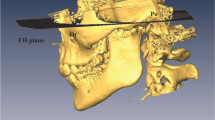

Facial angle (angle between the Frankfort plane and the sella–pogonion)

Occlusal plane angle (angle between the Frankfort plane and the occlusal plane)

Y‑axis (angle between the Frankfort plane and the sella–gnathion)

To examine the anteroposterior positional relationship of the condyle in the glenoid fossa, x/X (anteroposterior ratio of the condylar position in the X‑axis) was calculated in our previous study.

The x/X ratio in class 3 (n = 30) was 0.573 and that in class 1 (n = 17) was 0.523. There was a significant difference between the two groups.